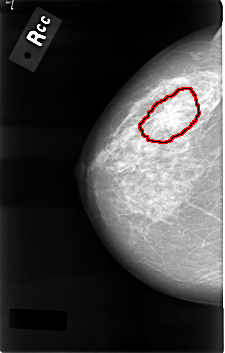

C_0001_1.RIGHT_CC

RIGHT_CC LINES 4584 PIXELS_PER_LINE 2920 BITS_PER_PIXEL 12 RESOLUTION 50 OVERLAY

FILE: C_0001_1.RIGHT_CC.OVERLAY

TOTAL_ABNORMALITIES 1

ABNORMALITY 1

LESION_TYPE MASS SHAPE IRREGULAR MARGINS SPICULATED

ASSESSMENT 5

SUBTLETY 5

PATHOLOGY MALIGNANT

TOTAL_OUTLINES 1

BOUNDARY